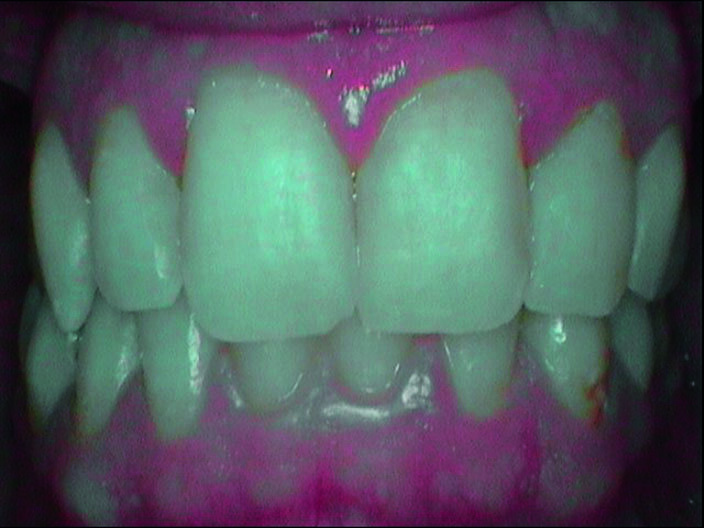

Durante l’esame obiettivo (Figg. 1a, 1b) rileviamo il danno iatrogeno da terapia ortodontica precedente alla visita e riscontriamo la presenza di processo carioso ICDAS 3 in zona 33 e in zona 47, white spots in zona 31 e 41. Durante l’esame obiettivo, l’ausilio della videocamera intraorale Sopro-Care (Acteon) permette, tramite filtri appositi, di evidenziare in modo rapido e accurato le zone di demineralizzazione e le aree infiammate e di mostrarle al paziente in real time, rendendolo attivamente partecipe e consapevole della situazione clinica (Figg. 2a-2f). I ricercatori del Baylor College of Dentistry hanno dimostrato che il 23,4% dei pazienti ha sviluppato almeno una white spot lesion durante il trattamento ortodontico.

Prima del trattamento abbiamo applicato un rilevatore di placca alla fluoresceina Plac-o-Tect (Directa) per evidenziare la topografia della presenza di biofilm batterico nel cavo orale. Osserviamo la topografia del biofilm batterico presente e condividiamo con il paziente i siti più ritentivi di biofilm batterico in modo da avere una comunicazione non verbale del rivelatore, utile per il rinforzo motivazionale del paziente con l’obiettivo di migliorare l’efficacia dell’igiene orale domiciliare (Fig. 3).

La metodica D-BIOTECH è applicabile nella terapia parodontale non chirurgica, come approccio clinico meccanico o manuale nel deplaquing e nel debridment. Tale approccio permette di eseguire un lavoro minimamente invasivo poiché l’operatore può strumentare con polishing selettivo, airpolishing, ablatori o strumentazione manuale seguendo esclusivamente la topografia del biofilm batterico, poiché intercetta visivamente i siti più a rischio di infiammazione attraverso la colorazione del rivelatore.

La comunicazione non verbale visiva di questo approccio clinico nuovo permette un lavoro sicuramente più ergonomico per l’operatore, che sceglierà lo strumento o la tecnica operativa più performante per strumentare unicamente dove sono presenti biofilm batterico e discromie acquisite (Fig. 5).